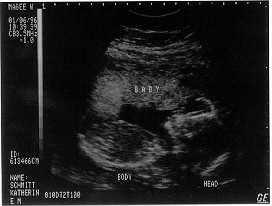

Pre-Baby Pictures

Isn't modern technology wonderful? It lets you put pictures of your kid on the Internet even before they're born!

These pictures are not for diagnostic purposes

Picture 1 Picture 2